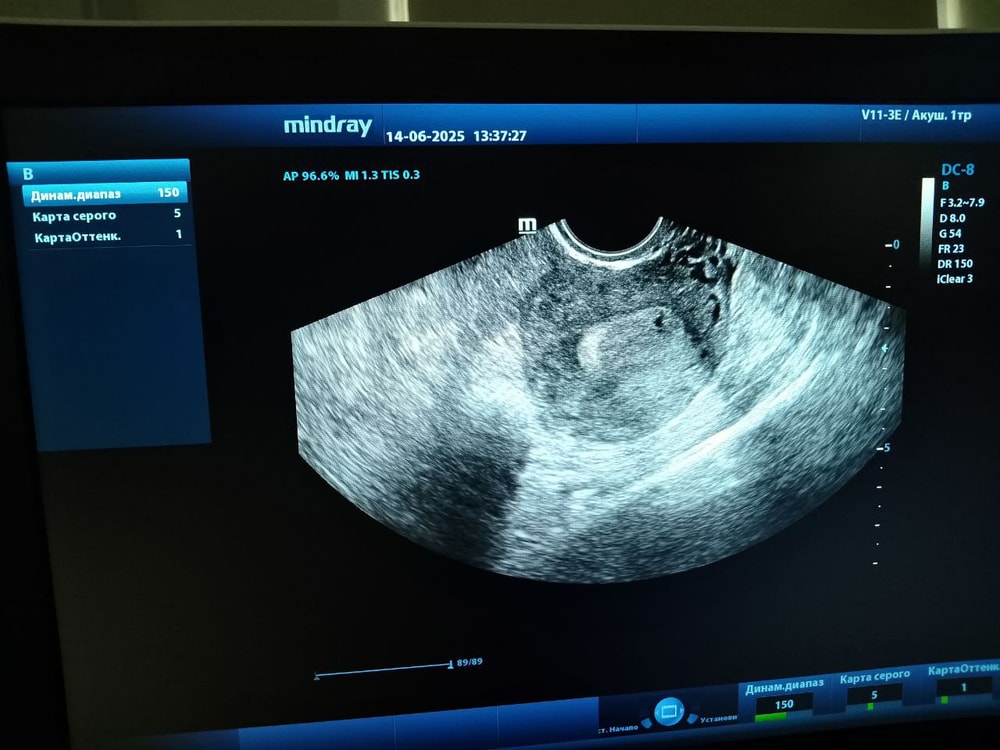

Дарья

Настена, я не говорила врачу про хгч это во первых,во вторых там искать не нужно было ничего,сразу было видно)

Дарья , ну не возможно на хгч 200-300 +/- ничего увидеть. Невозможно. Это ерунда. Либо 1) хгч в лаборатории не верно дали 2) это не пя. А например, маленькая миомка. Их часто путают.

Иначе никак.

Настена, через недельку конечно ещё раз схожу посмотрю,но мне врач сказала что буквально вот только прикрепление было.Вы конечно можете думать как вам угодно)Я шла за подтверждением маточной,я подтверждение получила)

Дарья , конечно идите смотреть.

Я не думаю как мне угодно. А опираюсь на мед статьи. В любом случае удачной вам беременности. Но если передадите завтра хгч и оно менее 1000, то узиста я бы сменила.